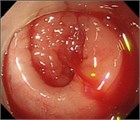

1. 大腸憩室炎と大腸憩室出血の典型例

1. 大腸憩室出血の治療

1. バンド結紮術:クリップ法と異なる内視鏡止血法として、高い止血効果が報告されているバンド結紮術がある。視認したSRHを吸引し、憩室を反転させた状態でバンドによる結紮を行う処置法である。この方法は、クリップを展開・操作するスペースが確保できない憩室出血病変に対して有用である。一方、クリップ法とは異なり、SRHからずれてバンドが結紮される場合には、追加のバンド結紮術を施行することが困難となる。バンド結紮術は腸管穿孔の有害事象が複数例報告されているため、注意が必要である。

1. 留置スネア法:EDSLは留置スネアを用い、内視鏡の再挿入を必要としない新たな止血法である。EDSLは結腸憩室出血の治療において有用かつ安全であることが示されている。